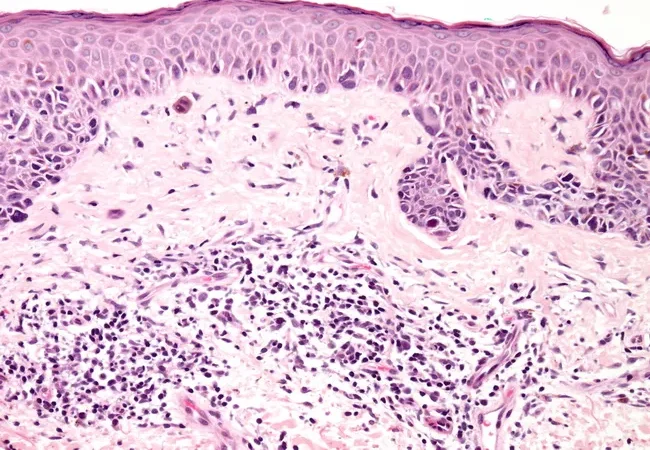

Lentigo maligna’nın tanısı genellikle cilt muayenesi ve biyopsi yoluyla konur. Dermatologlar, hastanın cildindeki pigment değişikliklerini inceleyerek şüpheli alanlar üzerinde biyopsi yaparlar. Biyopsi, hastalığın ne kadar ilerlediğini ve kanser hücrelerinin var olup olmadığını belirlemeye yardımcı olur.

Patolojik İnceleme: Biyopsi örneği, patoloji uzmanları tarafından mikroskop altında incelenir. Hücrelerin yapısı, büyüme hızı ve kanserin yayılma durumu analiz edilir.